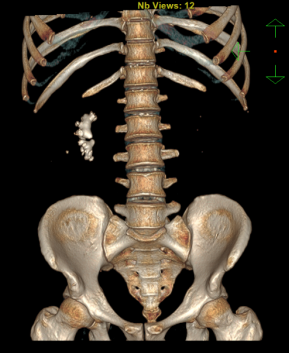

“医生,您帮我看看,我这样的情况能不能不在肾上‘打孔’?”34岁的姚先生拿着自己的CT报告,一脸焦虑地走进市中医医院泌尿外科。报告显示,他的右肾里藏着一颗铸型结石,形状不规则,几乎填满了肾脏空间。外院医生曾建议他做“经皮肾镜碎石取石术”——一种需要在腰部穿刺造瘘的微创手术。一想到术后身上要带着一根肾造瘘管好几天,姚先生犹豫了。泌尿外科副主任杨泽敏仔细阅片后,提出了一个更让他安心的方案——利用先进的高清软镜系统进行“无创清石”,从自然通道进入,碎石的同时直接吸出,体表不会留任何伤口。

手术当天,在高清电子软镜的引导下,杨泽敏团队开启了一场精准的“体内排雷”。软镜纤细灵活,前端可弯曲,顺着尿道、膀胱、输尿管这一自然通道,轻松抵达肾脏深处,就连最隐蔽的肾盏也一览无余。为避免输尿管损伤,所有操作都在一层“保护套”——输尿管导引鞘内进行。此次手术使用的更是市中医医院特有的“智能武器”:末端可弯曲负压吸引鞘。

当屏幕上的结石清晰可见,钬激光精准出击,将坚硬的结石瞬间粉末化。与此同时,负压吸引装置同步启动,将击碎的结石微粒迅速吸出体外。由于吸引鞘的末端可主动弯曲,医生能轻松调整方向,精准对准目标,大大提高了清石效率。手术全程,肾盂内部始终维持稳定的低压状态,不仅安全,也提升了患者的舒适度。

效果展示

激光碎石

吸出结石

结石样本